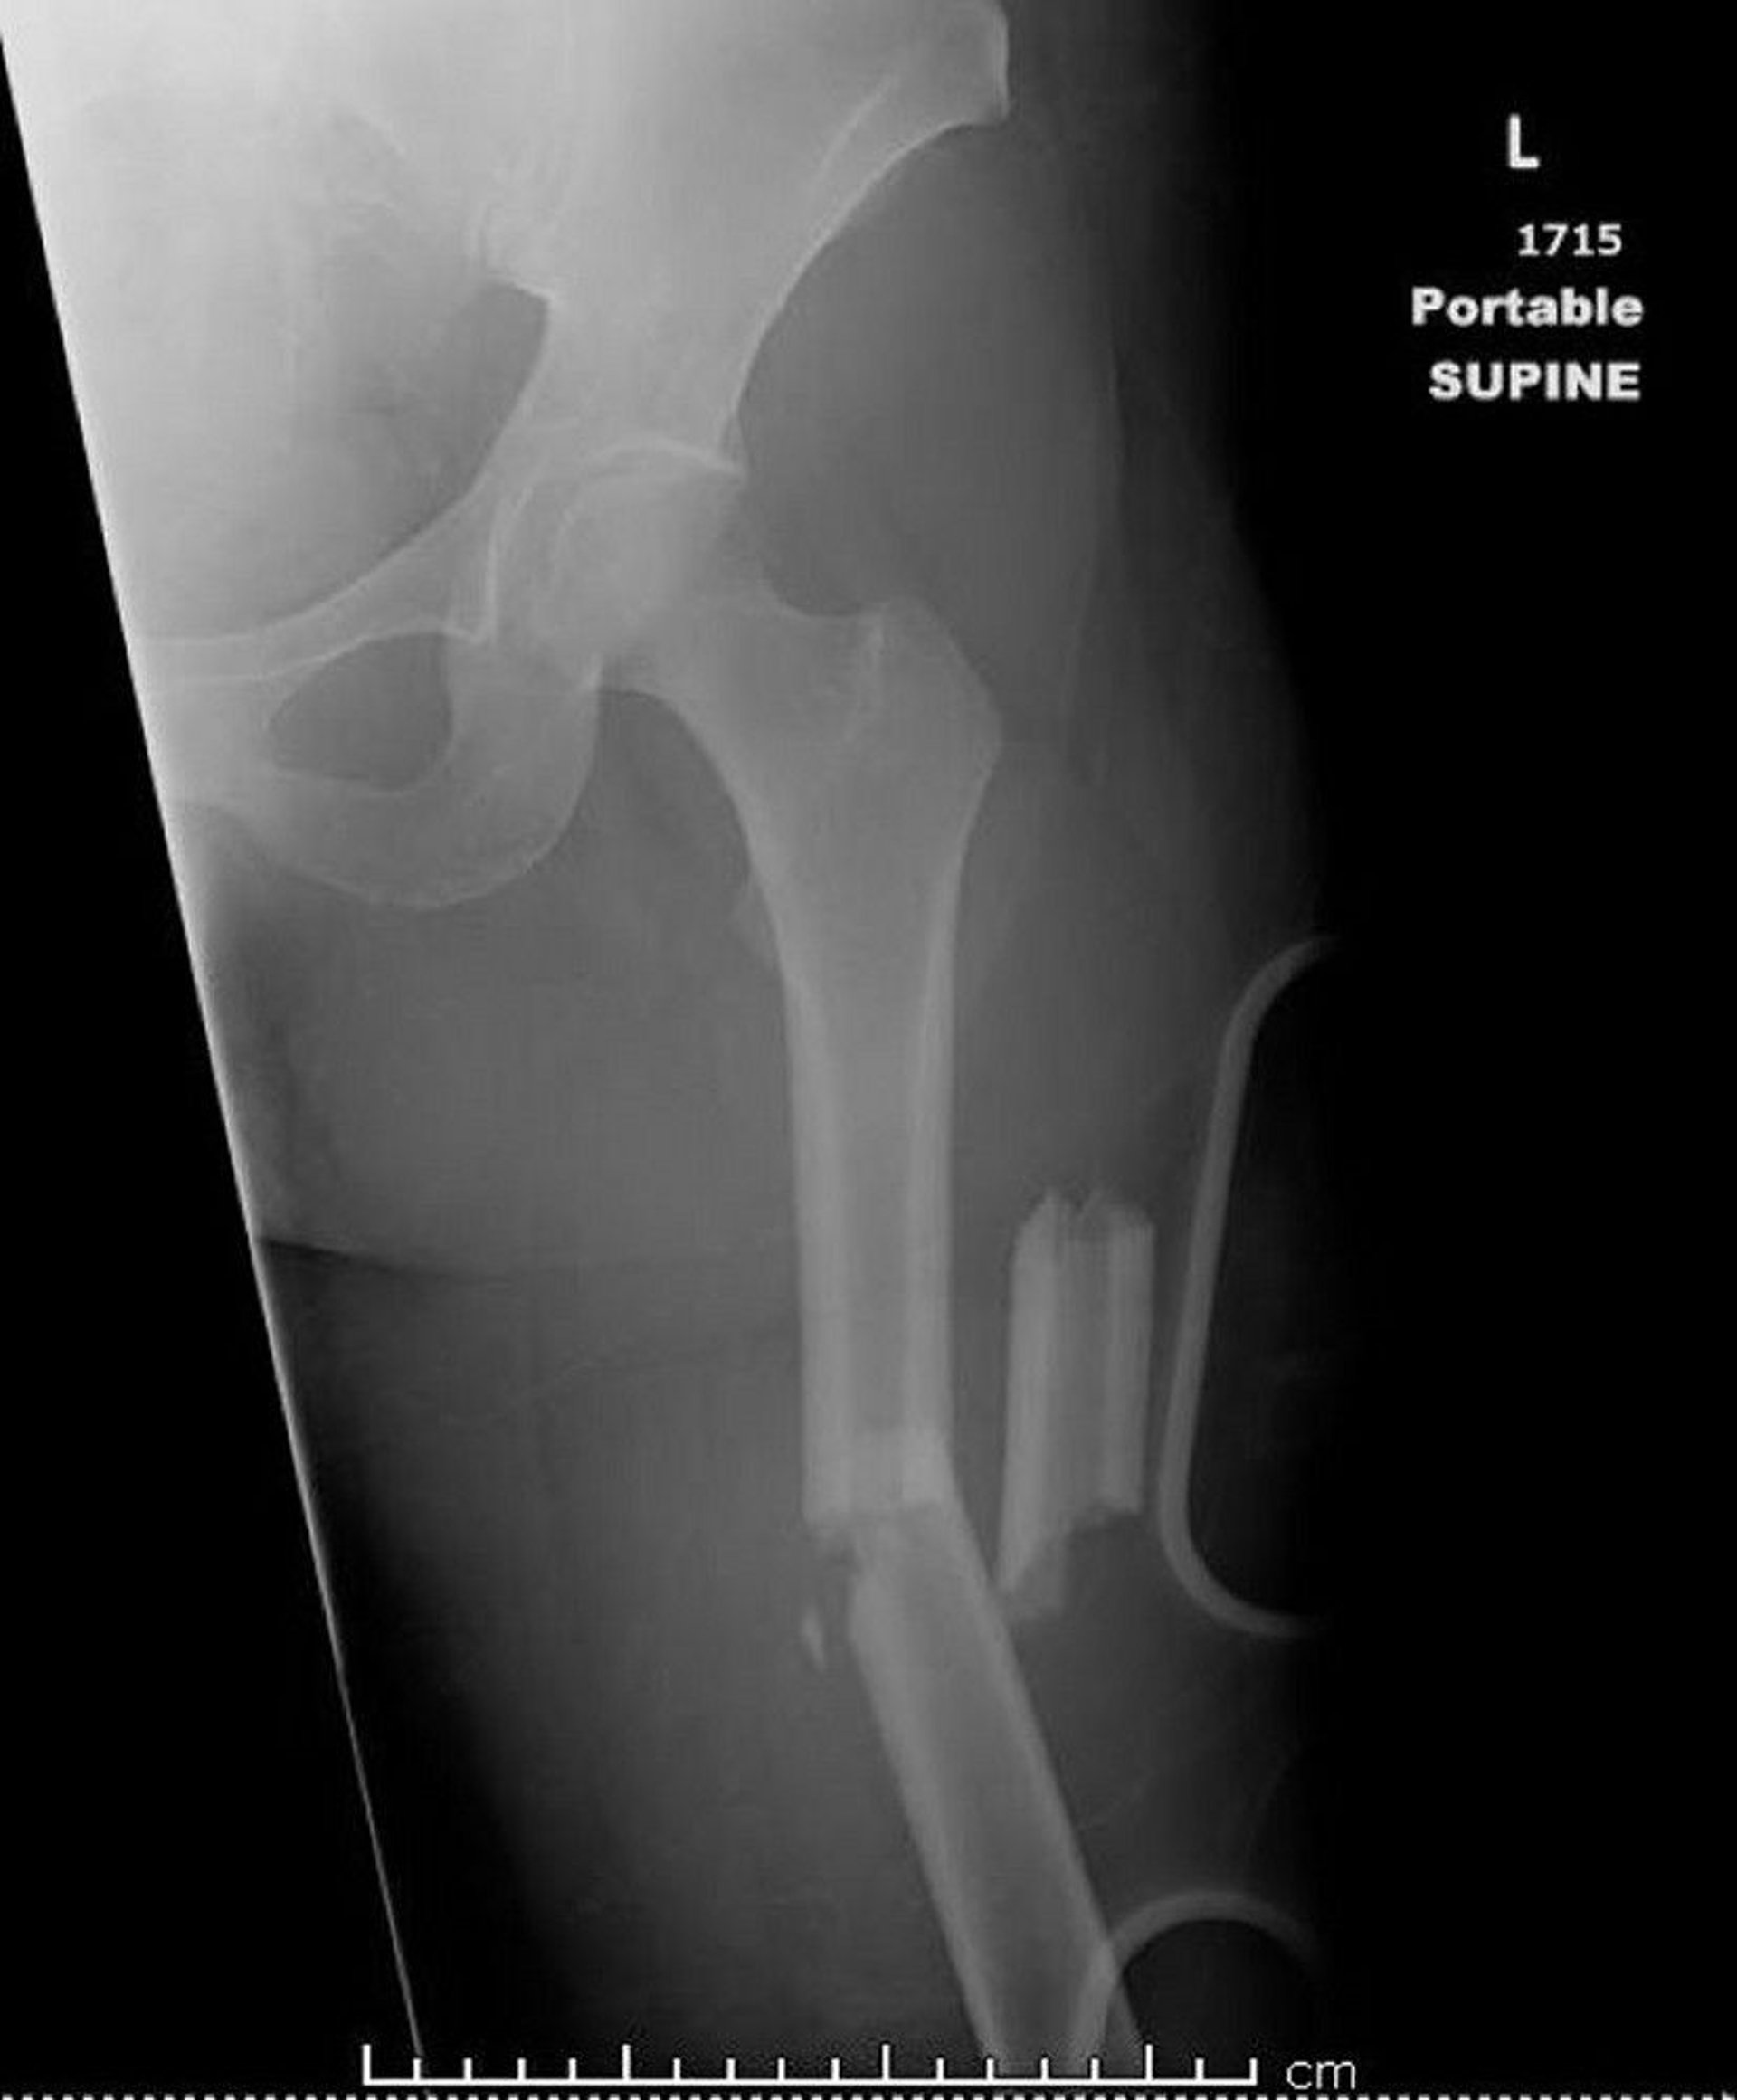

This image shows a comminuted, angulated, and shortened midshaft femur fracture.

Image courtesy of Danielle Campagne, MD.